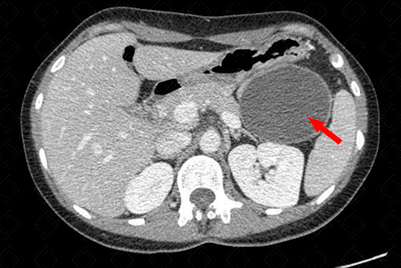

Descrição das figuras: Paciente do sexo feminino, 45 anos, realizou tomografia computadorizada do abdome com contraste venoso, fase portal evidenciando extensa lesão hipodensa, com realce parietal e periférico pelo meio de contraste, na cauda pancreática (setas vermelhas). O diagnóstico pela história clínica e características de imagem é sugestiva de cistoadenoma mucinoso. [cms-watermark]

• Tomografia computadorizada do abdome: O bservaremos lesão hipodensa, de densidade cística, com realce na parede do cisto, localizada, preferencialmente, no corpo/cauda pancreáticos (f iguras acima) .